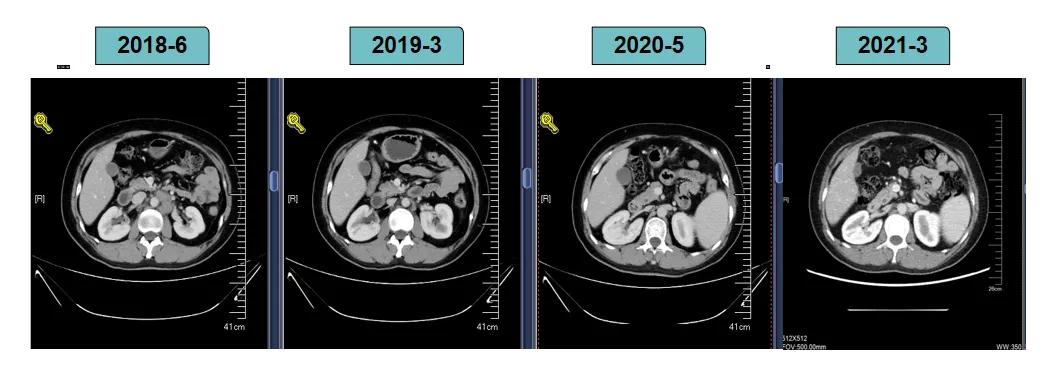

影像学评估-腹膜后淋巴结:

2018-7-17成功入组ELAINA临床研究(试验方案编号:BO29919),IWRS分配随机号3210。于2018-7-17开始接受T-DM1 3.6mg/kg(252mg)治疗,并间断对其进行疗效评估。现阶段患者PFS达近40个月。

靶病灶:腹主动脉左侧和下腔静脉右侧淋巴结

非靶病灶:肝左叶、肝右前叶下段;纵膈胸骨后淋巴结节;前上纵膈淋巴结;腹膜后小淋巴结